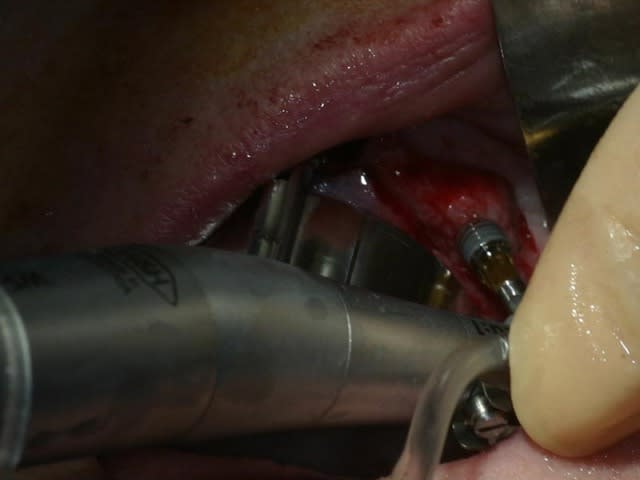

bon, toujours aussi speed je suis, mais après certaines réclamations, et malgrès ma réticence à poser un cas non "consolidé", voici en avant première mon premier all on 4, version photos ratées et non retouchées, mais... speed je suis je vous disais ;)

sto le bla bla, et pasons le diaporama... bon voyage au pays de la mise en charge immédiate totale au maxillaire de fille carole sur dame ginette, une patiente en or que j' adore, et pour qui je suis très très heureuse d' avoir pu réaliser cette chirurgie et la première étape prothétique.....

Tu as utilisé des Nobel Speedy si je ne me trompe pas.

Tu as eu un couple final de 50N au maxillaire ? Si c'est le cas, bravo.

Peux tu nous en dire un peu plus sur les implants, leurs diamétres et leur longueurs ?

du 4 par 15 ?